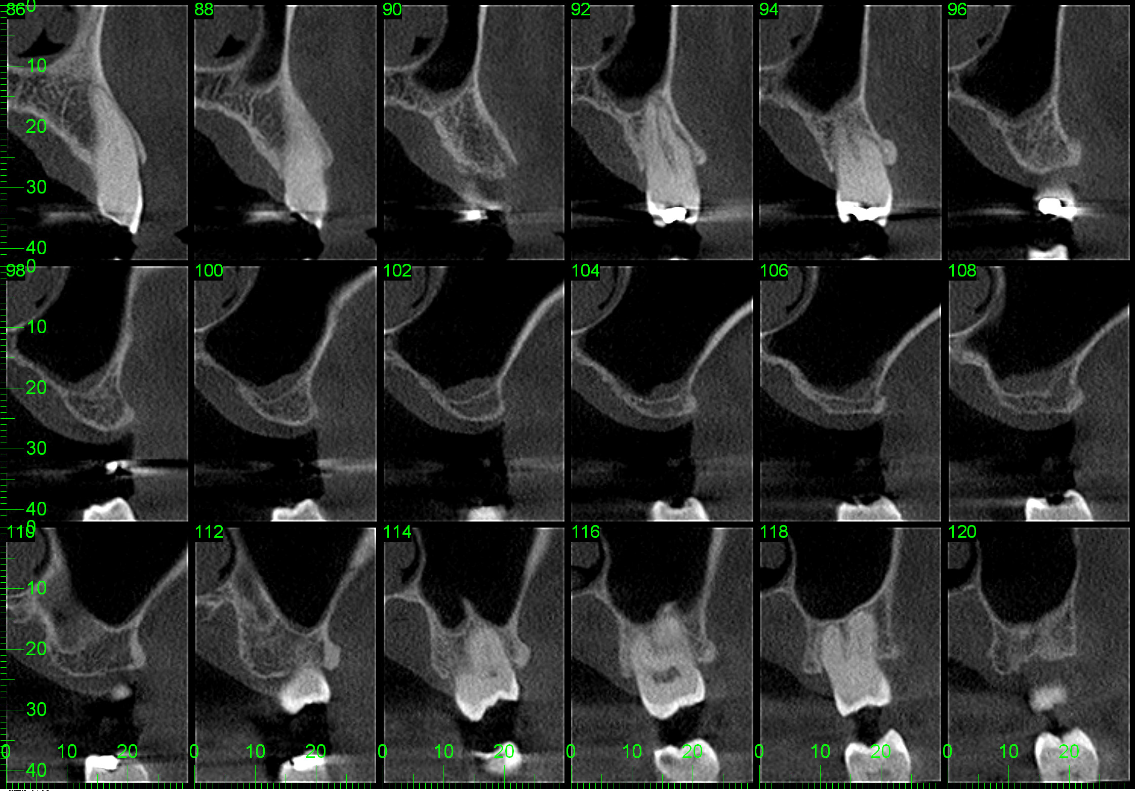

This healthy 64 year old male patient presented with missing teeth 25 and 26, which had been removed some years ago due to periodontal disease. Despite excellent oral health in general and thick biotype at the local sites of interest, there had been expansion of the maxillary sinus leading to only 4 mm of bone height at site 26. See diagnostic CBCT radiograph below.